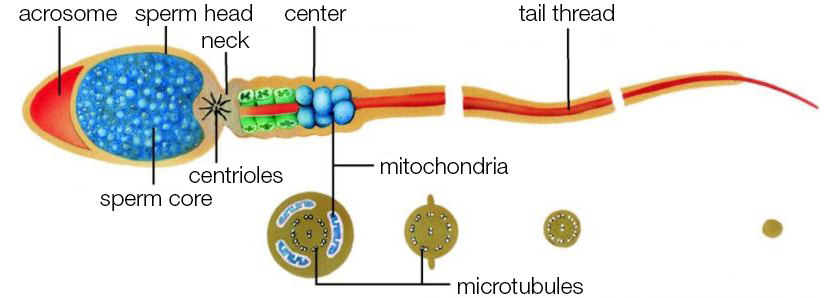

HOW SPERM PRODUCTION WORKS

Hormones play a decisive role in sperm production (=spermatogenesis). The pituitary gland generates a hormone known as follicle stimulating hormone (FSH). The luteinizing hormone (LH) is generated at the same time. While both hormones lead to the maturation of egg cells in women, in men they are responsible for the formation of sperm cells.

In the course of sperm cell maturation, the body requires some natural herbs roots at different development stages. The optimal prerequisites for normal and healthy spermiogenesis are only guaranteed if these special vital roots are provided.